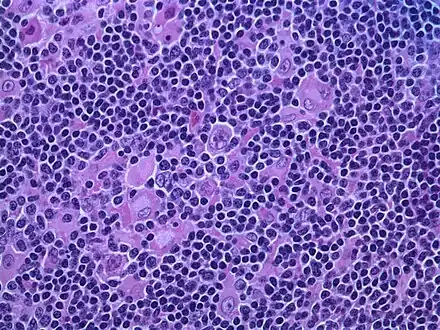

| Micrograph of a lymph node biopsy showing nodular lymphocyte predominant Hodgkin lymphoma, with the Reed–Sternberg cell variant that has a popcorn-shaped nucleus (left-bottom of image). H&E stain. | |

Hodgkin lymphoma, nodular lymphocyte predominant (low power view). Notice the nodular architecture and the areas of "mottling". (H&E) Hodgkin lymphoma, nodular lymphocyte predominant (high power view). Notice the presence of LP cells, also known as "popcorn cells". (H&E)

Hodgkin lymphoma, nodular lymphocyte predominant (high power view). Notice the presence of LP cells, also known as "popcorn cells". (H&E)

The characteristics of NLPHL differ from classical Hodgkin lymphoma (cHL).[9] Lymphocyte predominant (LP) ("popcorn") cells are present embedded in nodules consisting of B cells[10] and other reactive cells (mainly reactive T cells).[9] Reed-Sternberg and Hodgkin (RSH) cells are rarely seen, and immunohistochemistry shows a different pattern on the malignant cells; RSH cells typically express CD15 and CD30, whereas LP cells lack expression of these markers, but express B cell markers like CD20, CD22, and CD79a and also express the common leukocyte antigen CD45, which is uncommon on RSH cells.[9] The LP cells have scant cytoplasm and one folded or multilobated nuclei with prominent, mostly basophilic nucleoli.[10] Expert pathology review of multiple morphologic and immunophenotypic features[10] including the use of immunohistochemistry is essential.[11][12]